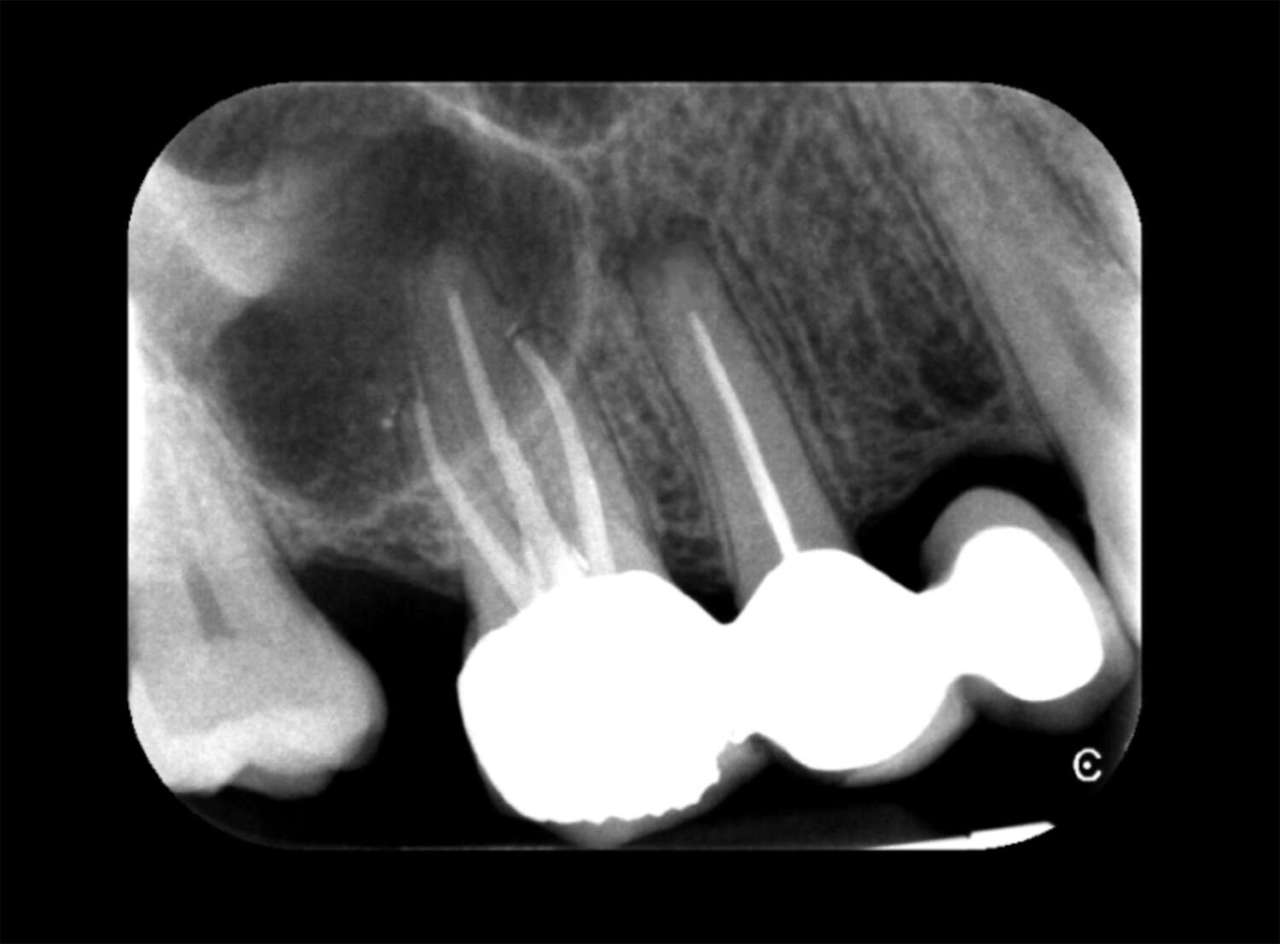

Successivamente all’interno della cavità viene inserita una piccola quantità di EDTA gel, attivato ultrasonicamente e, in seguito, una piccola quantità di NaOCl gel, con una ulteriore attivazione ultrasonica. Conclusa l’applicazione della tecnica RUA, la retrocavità viene esaminata ad alto ingrandimento. Dopo aver verificato la buona detersione, si procede alla retro-otturazione utilizzando MTA (Figure 5a-b). La radiografia post-operatoria non rileva alcuna criticità (Figura 6).

A distanza di otto mesi dall’intervento, si esegue un controllo radiografico 3D per valutare la reale guarigione dell’elemento 1.5. La CBCT evidenzia la riformazione della corticale vestibolare a livello apicale e la scomparsa della lesione periapicale (Figure 7a-b).